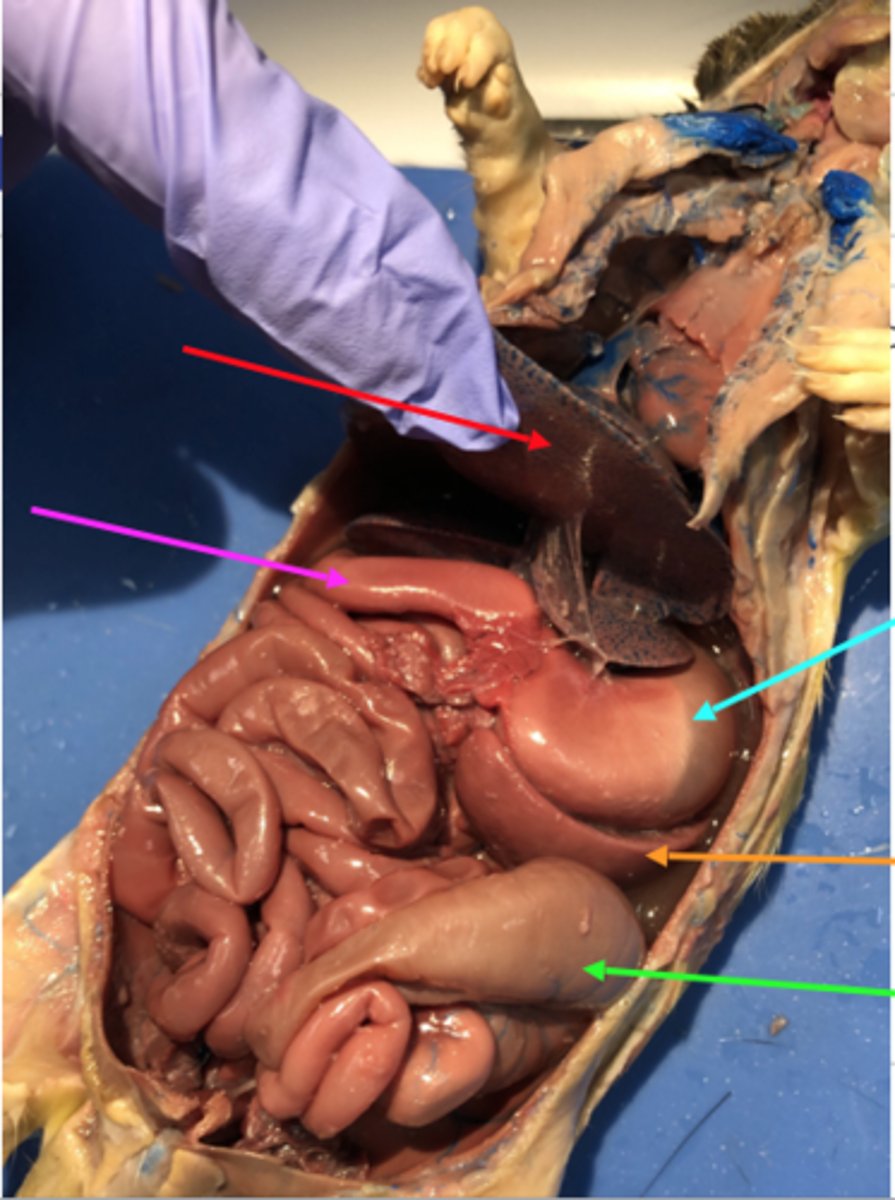

stomach

duodenum

jejunum

ileum

mesentery

large intestine

cecum

ascending colon

transverse colon

descending colon

sigmoid colon

Apendix

liver

pancreas

spleen